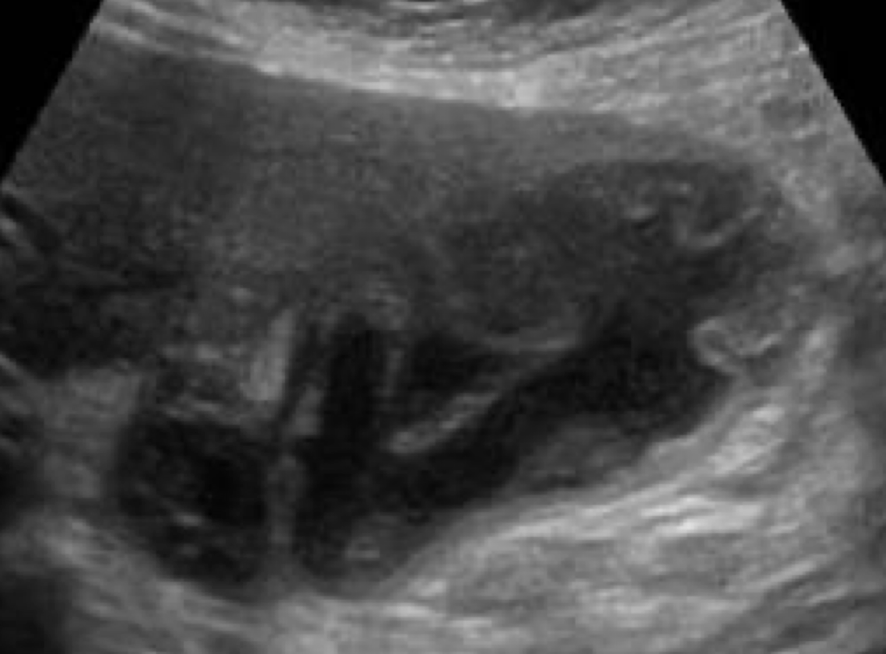

SONO: Caroli’s disease

multiple cystic structures in the track of ducts (in the area of the ductal system) that converge at portal hepatitis

“Central dot” sign = dilated duct surrounding the adjacent HA and PV

one Mickey ear is bigger than the other

??

Type 5 choledochal cysts (Caroli’s disease)